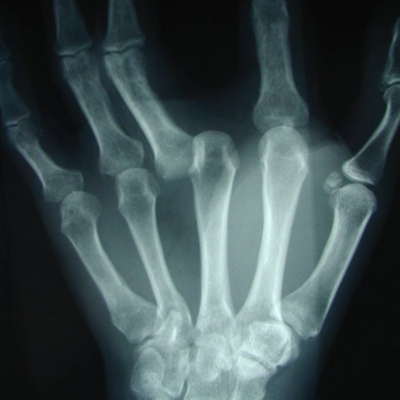

Click on an image below to view more info.